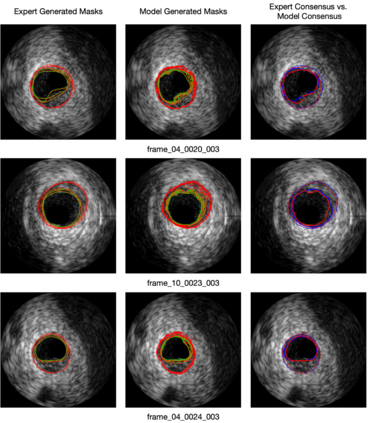

Medical imaging, including MRI, CT, and Ultrasound, plays a vital role in clinical decisions. Accurate segmentation is essential to measure the structure of interest from the image. However, manual segmentation is highly operator-dependent, which leads to high inter and intra-variability of quantitative measurements. In this paper, we explore the feasibility that Bayesian predictive distribution parameterized by deep neural networks can capture the clinicians' inter-intra variability. By exploring and analyzing recently emerged approximate inference schemes, we evaluate whether approximate Bayesian deep learning with the posterior over segmentations can learn inter-intra rater variability both in segmentation and clinical measurements. The experiments are performed with two different imaging modalities: MRI and ultrasound. We empirically demonstrated that Bayesian predictive distribution parameterized by deep neural networks could approximate the clinicians' inter-intra variability. We show a new perspective in analyzing medical images quantitatively by providing clinical measurement uncertainty.